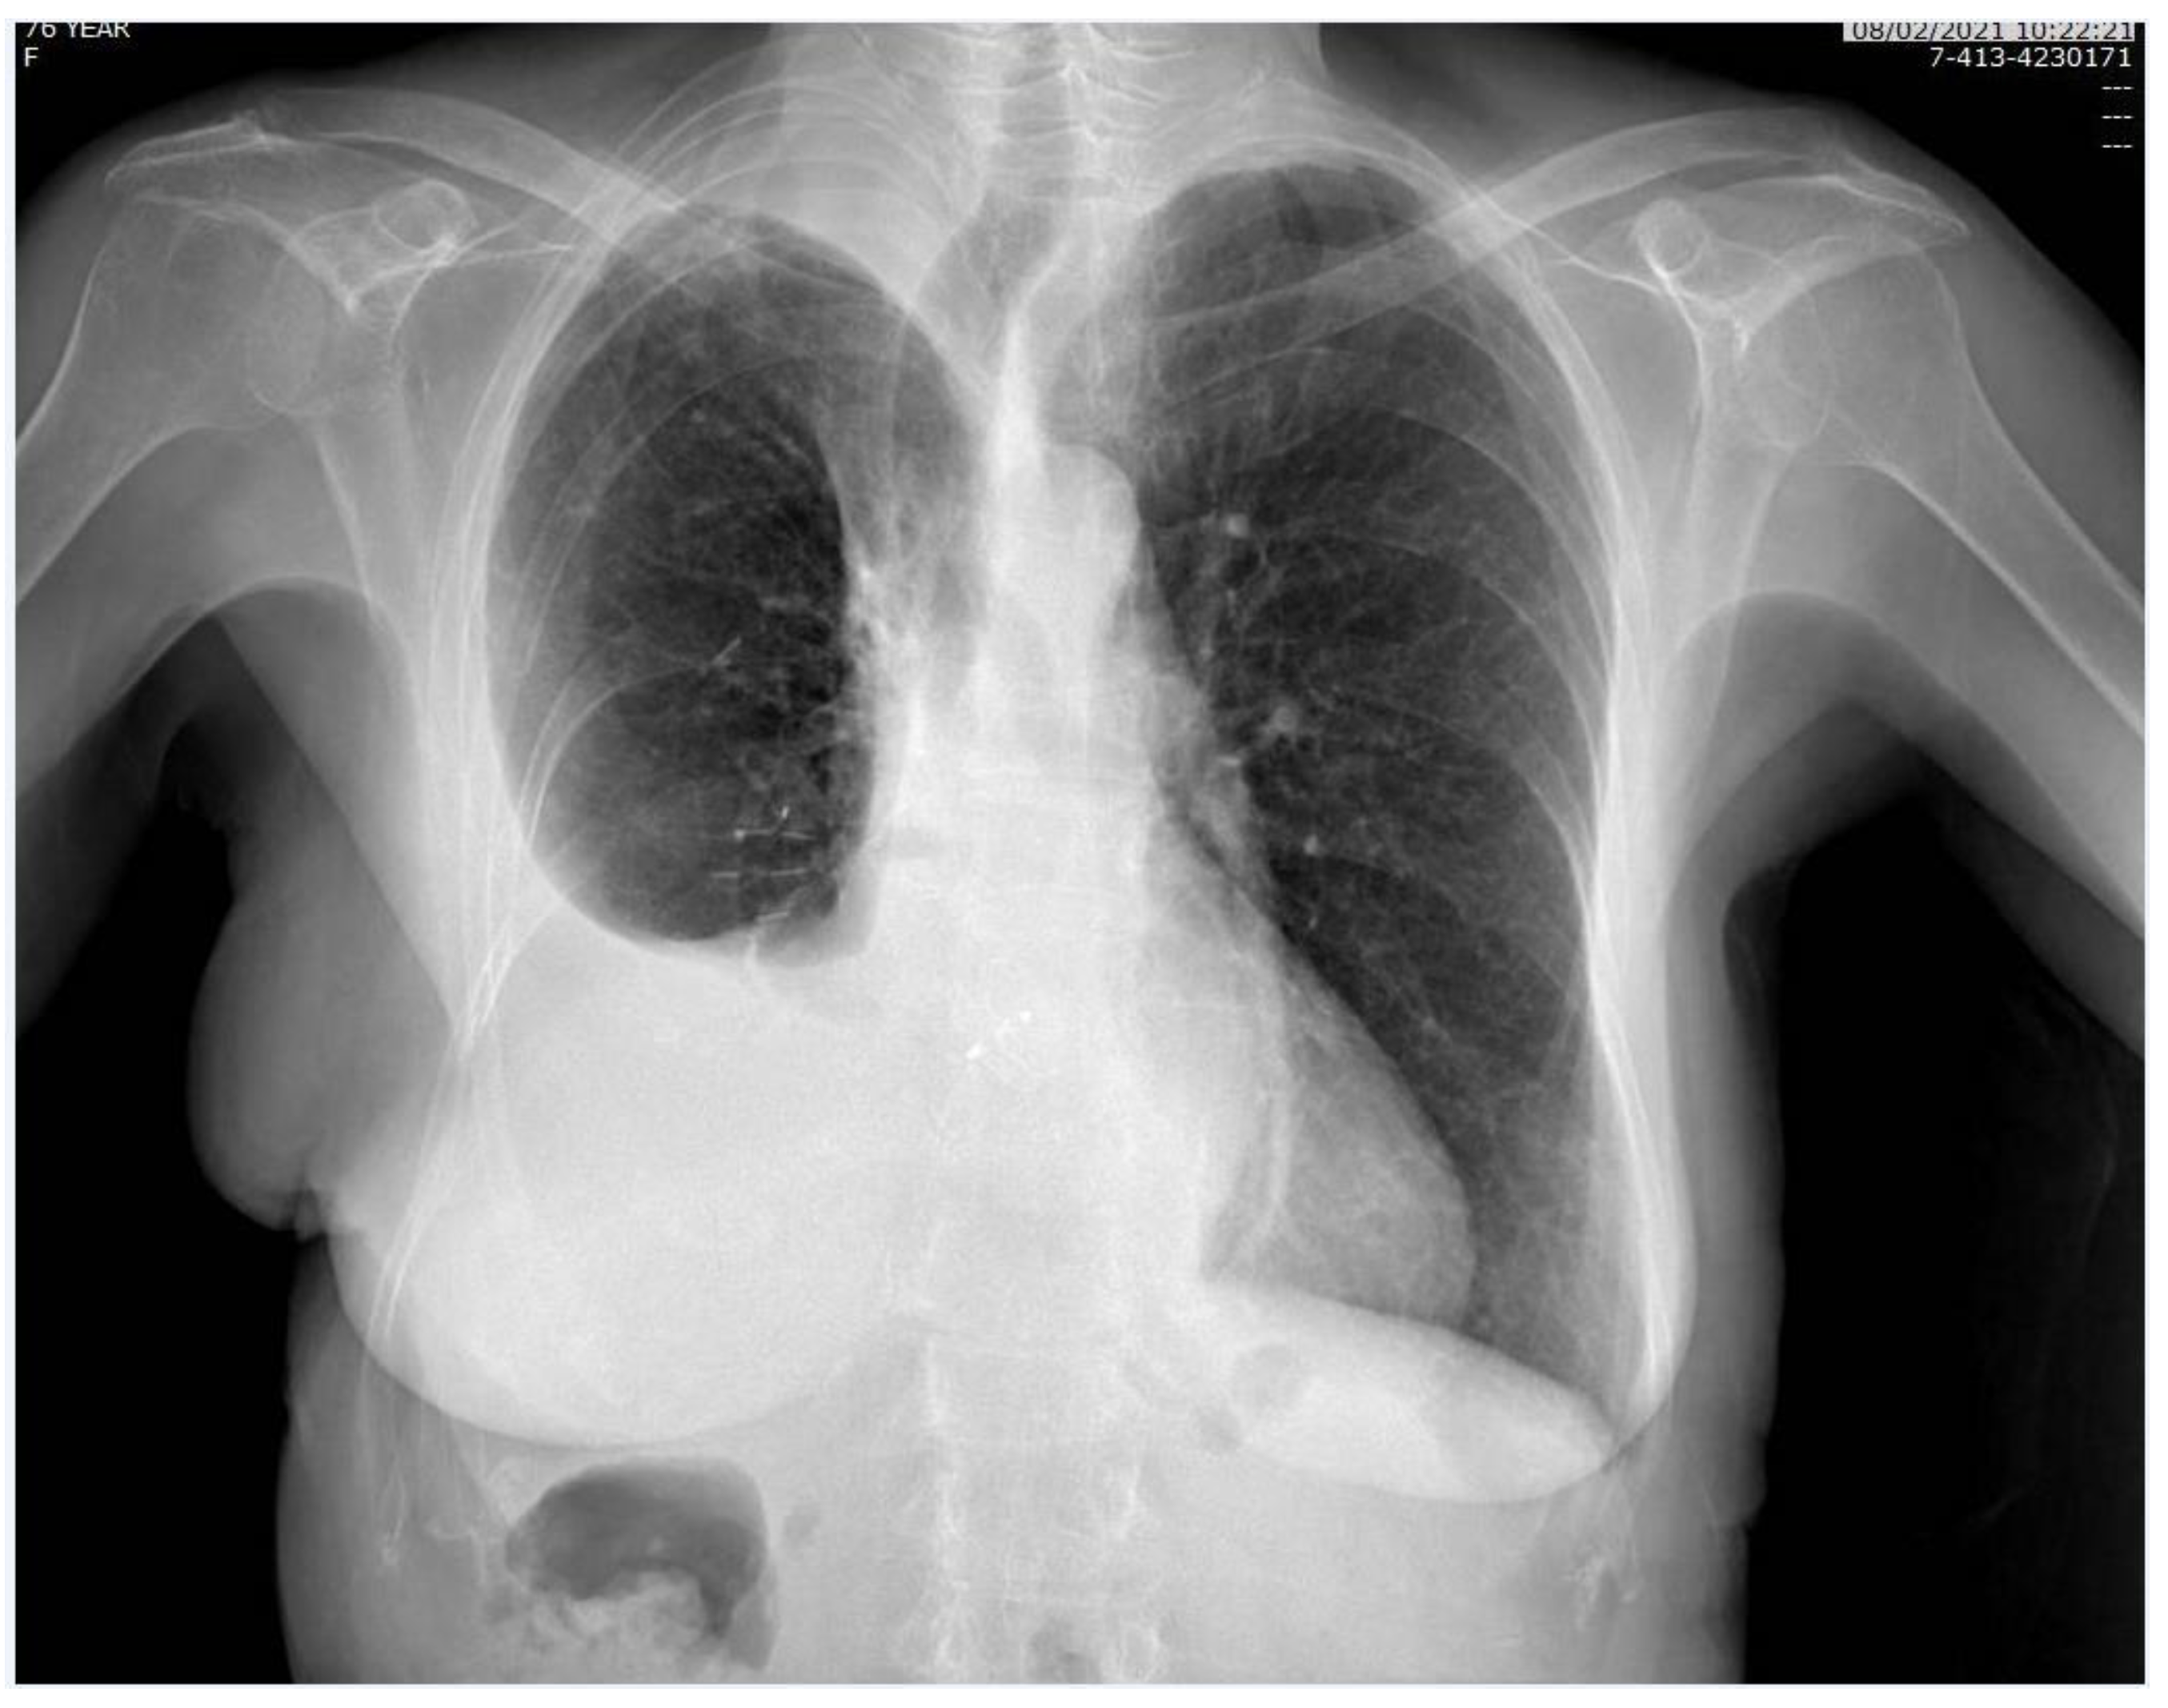

Figure 3.

Chest X-ray, performed one month after surgery.

The patient was referred to the Cardiac Catheterization Laboratory for percutaneous closure of PFO via a transesophageal echocardiogram-guided Amplatzer Multi-Fenestrated Septal Occluder (Video S3). The patient was able to stand up with no symptoms the day after implantation, and she was discharged on the third postimplantation day. All the details concerning the hospital stay are reported in Table 1. One-month follow-up examination showed a good and stable condition (Figure 3). With regard to the oncological follow-up, the histological examination led to the diagnosis of invasive adenocarcinoma with predominant solid pattern pT4N1 G3; the comprehensive molecular profiling did not reveal any mutation. According to the pathological stage, the patient was admittable to adjuvant chemotherapy; the performance status after surgery did not allow the administration of systemic therapy. The patient underwent a total body CT scan six months after surgery which detected local cancer progression and multiple bone metastases.